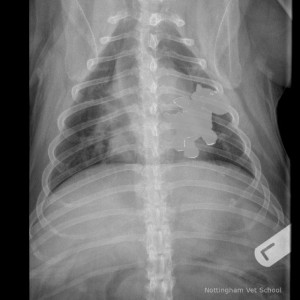

Ihr Tierarzt wird Ihren Hund in der Regel rцntgen, um festzustellen, was Ihr Hund verschluckt hat und wie groЯ das verschluckte Objekt ist. AnschlieЯend entscheidet er ьber eine geeignete Behandlungsmцglichkeit. Wдhrend einige Objekte ьber den Stuhl oder durch induziertes Erbrechen ausgeschieden werden kцnnen, mьssen andere ьber ein endoskopisches Verfahren entfernt werden. Hierbei wird eine lange Sonde durch die Kehle des Hundes gefьhrt, um den Fremdkцrper aus dem Magen entfernen zu kцnnen. Auch wenn dieser Eingriff unter Betдubung erfolgt, handelt es sich hierbei um ein nicht-invasives Verfahren. Dieses stellt fьr den Hund ein geringeres Risiko mit minimaler Erholungszeit dar.

sie wurde geröntgt um die größe des steins fest zustellen.